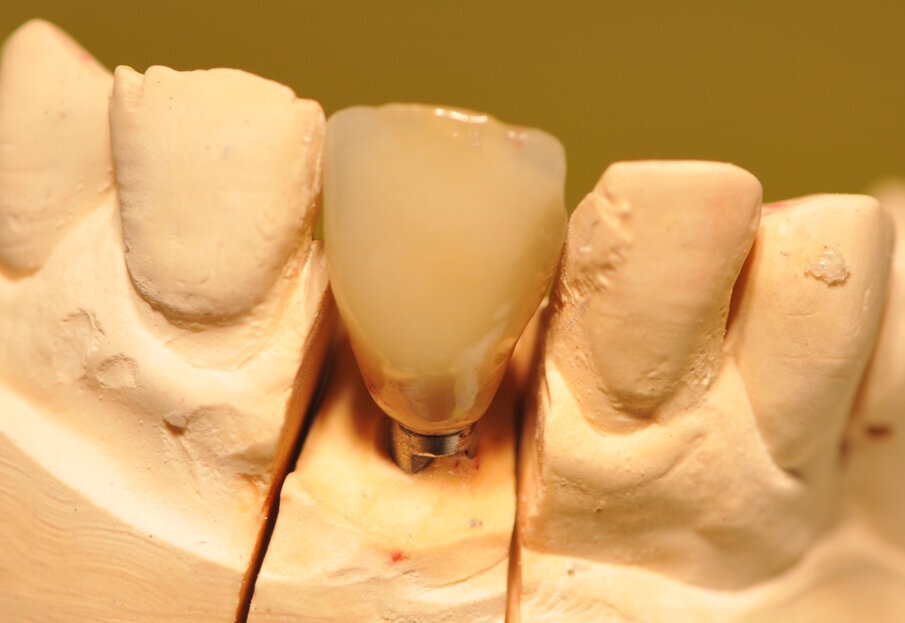

Paziente di sesso maschile di 60 anni di età giunto alla nostra osservazione per una edentulia parziale dovuta all’assenza dell’elemento 1,1. La situazione clinica è resa esteticamente e funzionalmente complicata dalla assenza dell’elemento 2,2 che considerato lo spostamento dei denti contigui comporta un aumentato spazio per la sostituzione protesica dell’elemento 1.1. Si effettua dopo rx di controllo il posizionamento di un impianto osteintegrato GTB diametro 3,6 x 9 mm ,con posizionamento, come da protocollo, 1,5 mm sottocrestale ed inserzione immediata di moncone easy abutment slim 3,4 x 7 mm altezza gengivale 3,5 mm. angolato a 10 gradi (Easy Abutment Slim – GTB Plan1Health Amaro, UD, Italy). Con l’ausilio di una cappetta easy si costruisce e si cementa, con tecnica extraorale, una corona provvisoria in resina acrilica con forma a pontic su elemento 1.1 in modo da eseguire un carico immediato e fornire al paziente una estetica immediata (Figg. 1-3). Dopo 12 settimane ad avvenuta osteointegrazione si provvede all’impronta definitiva eseguita a livello abutment con elastomero di precisione Aquasyl Monophase (Dentsply) e con idonea cappetta easy (GTB Plan1Health Amaro, UD, Italy). La stessa cappetta easy viene utilizzata dal laboratorio odontotecnico come cappetta da sovrafusione garantendo standard di precisione stabiliti industrialmente (Figg. 4-8). La corona costruita in lega preziosa e porcellana viene cementata dopo una settimana, fatte le prove estetiche e occlusali necessarie sul paziente. I controlli a distanza di 4 anni, sia radiografici che clinici, confermano la stabilità dell’osso intorno all’impianto e la mancanza di perdita di tessuto gengivale attorno allo stesso (Figg. 9-11).

Fig. 7_Analogo del moncone sul modello in gesso.

Fig. 8_Corona Definitiva in LP e Ceramica sul modello.